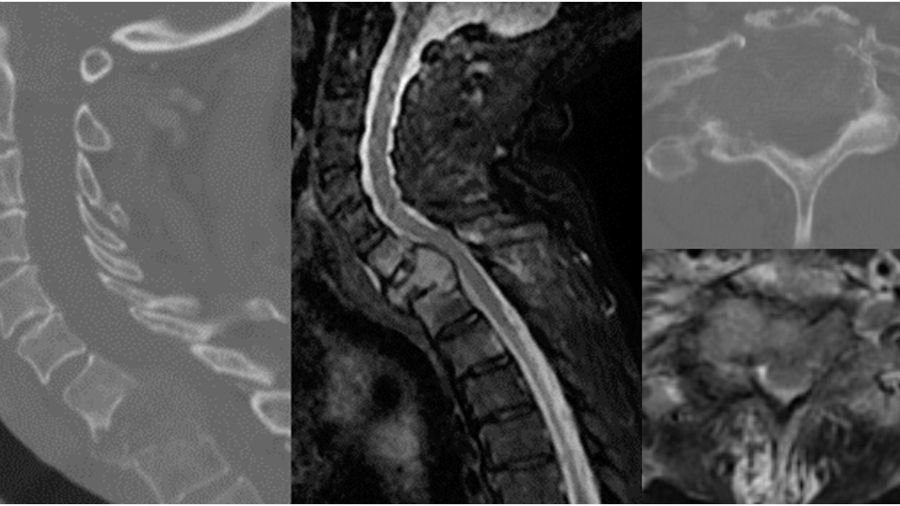

Case 1: A 46-year-old man presents with 3 months of weight loss, back pain, and cough. He is a non-smoker.

Chest imaging reveals a lung nodule consistent with NSCLC (adenocarcinoma) and molecular analysis reveals an EGFR mutation. There is a single metastatic lesion at L2 causing a pathologic fracture with greater than 50% loss of height and retropulsion. He is ambulatory and has pain-limited weakness 4/5 on the hip flexor. He has good performance status (ECOG 1) and his Spine Instability Neoplastic Score is 17. Given the recent diagnosis of NSCLC and the favorable EGFR mutation, patient is started on osimertinib and offered separation surgery plus stabilization.